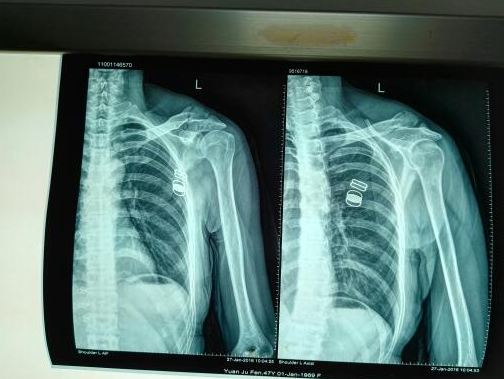

杭州尊龙凯时科技:肩胛骨骨折合并锁骨骨折的一站式3D打印扫描建模解决计划

随着医疗技术的不绝生长,3D打印和CT重建技术在骨科手术中的应用越来越广泛。杭州尊龙凯时科技作为一家一站式3D打印…

杭州尊龙凯时科技:专业解决肱骨大结节骨折,3D打印与CT重建

肱骨大结节骨折是一种较为常见的骨折类型,常爆发在运动损伤、交通事故等情况下。古板的手术要领虽然能够解决问题,但…